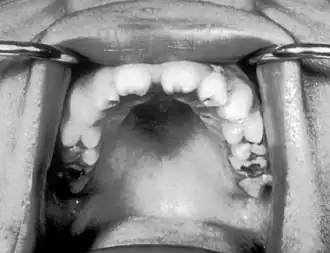

![]() Incisivos con muescas conocidos como dientes de Hutchinson que son característicos de la sífilis congénita | ||

- Dientes incisivos superiores romos conocidos como dientes de Hutchinson ¨

Un grupo de síntomas que se encuentra con frecuencia es la tríada de Hutchinson, que consiste en dientes de Hutchinson (incisivos con muescas), queratitis y sordera y ocurre en el 63% de los casos.[5]

- Tríada de Hutchinson, un conjunto de síntomas que consisten en sordera, dientes de Hutchinson (incisivos centrales superiores en forma de clavija con muescas centrales y muy espaciados) y queratitis intersticial, una inflamación de la córnea que puede provocar cicatrización corneal y ceguera potencial